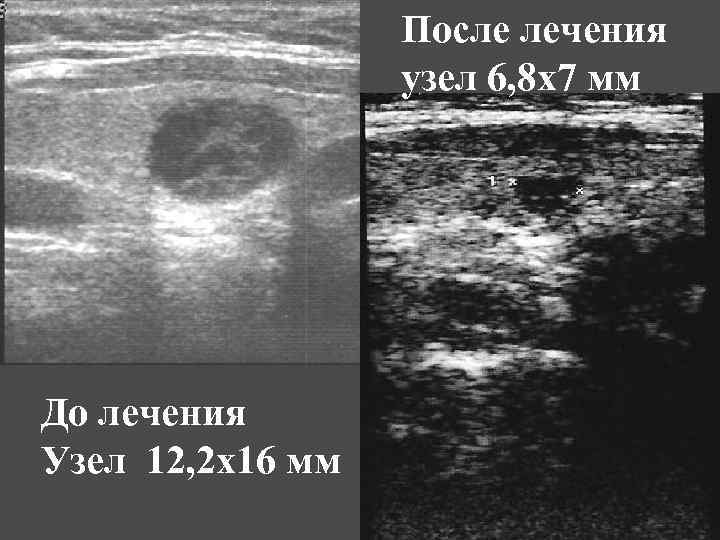

После лечения узел 6, 8 х7 мм До лечения Узел 12, 2 х16 мм